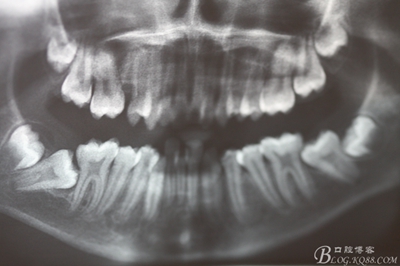

圖3. 這是患者的全景片影像檢查:看不清16與14之間是否有牙根遺留